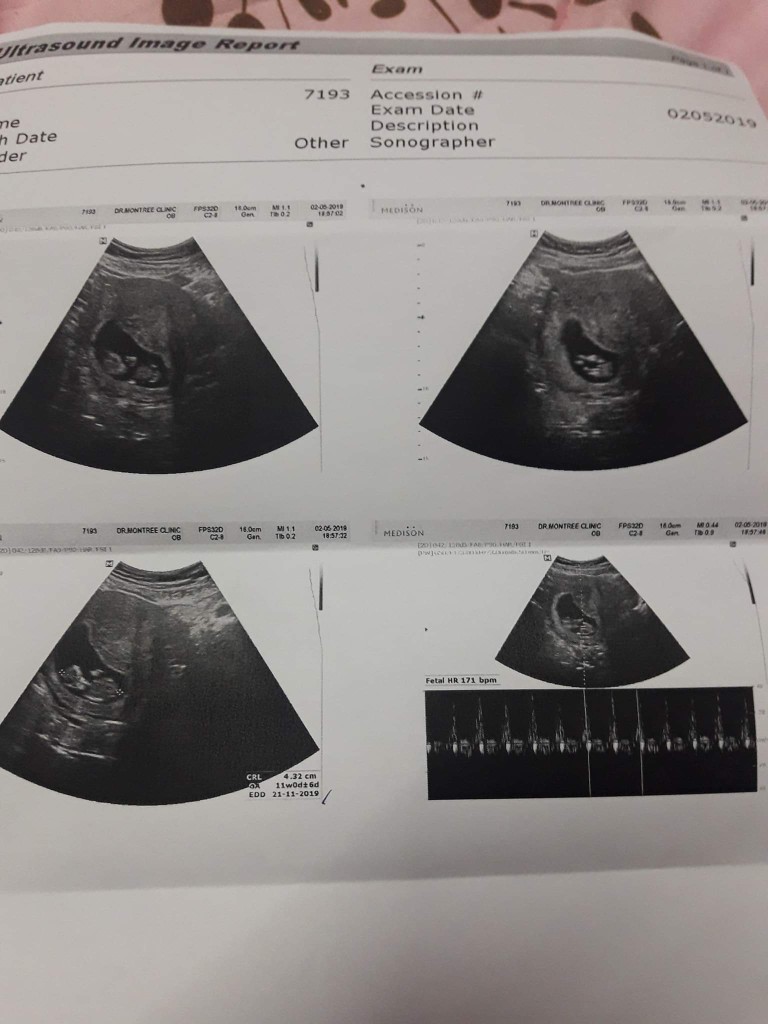

12W ค่ะ

11 วีค